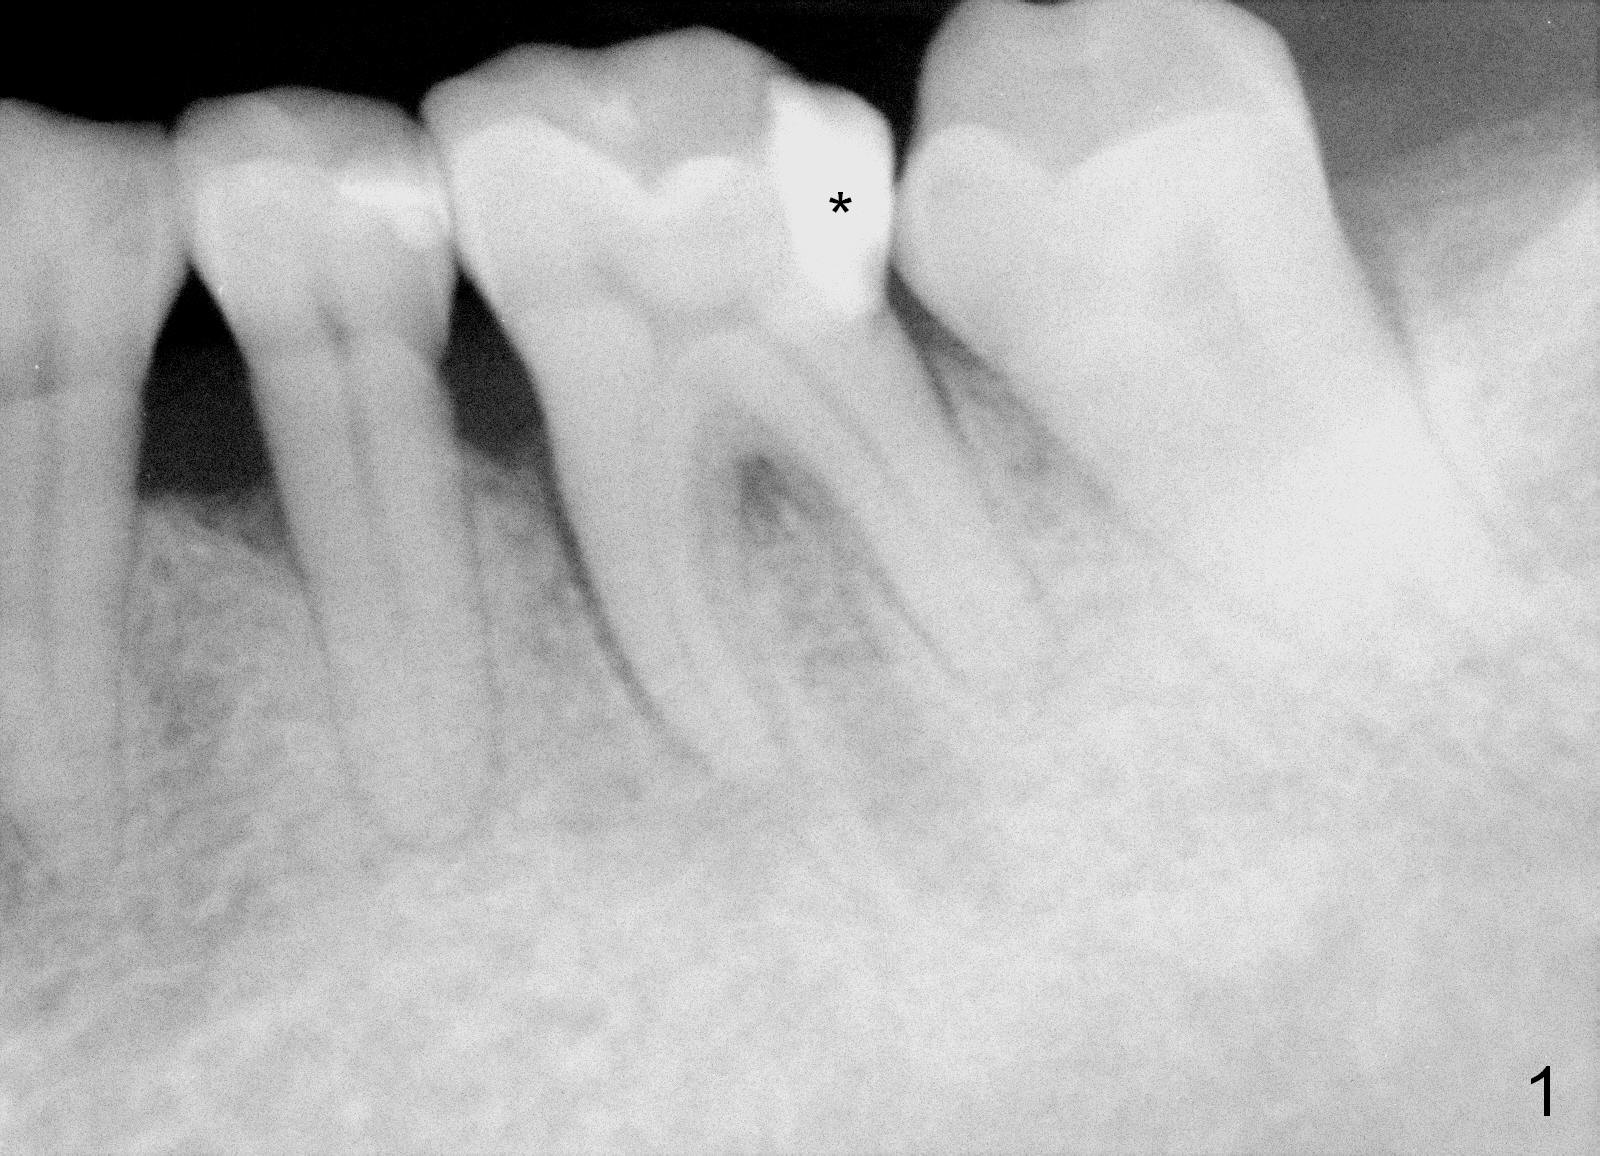

A 59-year-old lady has history of periodontal disease and bruxism. The tooth #19 has pulpitis after unsuccessful DO composite (Fig.1 *) and requires root canal therapy (Fig.2). Six months later, a fistula is found to communicate with the furca (Fig.3 *: gutta percha). Less than 3 years, the furca enlarges with symptoms of infection (Fig.4 *). She works out of state. The Principle of No Implant, No Extraction is adhered. Since she is of short statue, the bone height is relatively limited. A 6x14 mm tissue-level implant is appropriate (Fig.5, one piece). Sensor 1 may be proper for her small mouth. When the bottom of the socket is large and close to the Inferior Alveolar Nerve, can an immediate implant be placed?